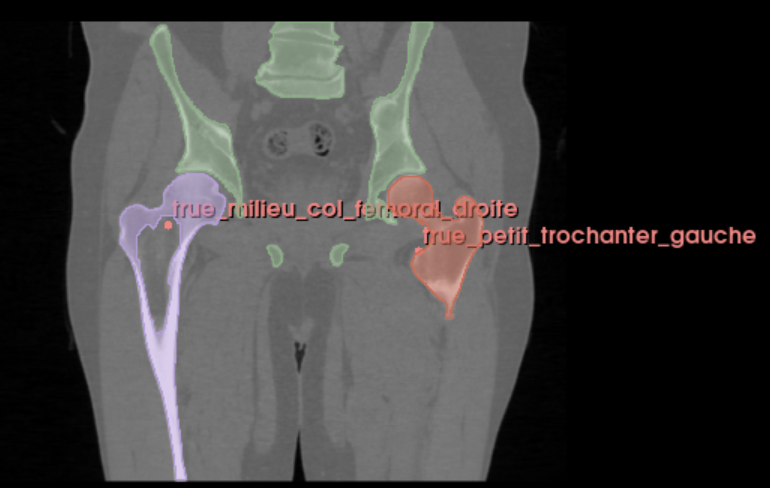

Neovision a développé une solution permettant la reconstruction 3D des os du membre inférieur et la détection des points anatomiques (landmarking). Nous nous sommes basés sur un algorithme de deep learning et sur les données standard en imagerie médicale DICOM (série de surface plane 2D superposées qui crée un volume).

Cette fonctionnalité consiste à automatiser la tâche de reconstruction effectuée manuellement par des spécialistes médicaux en utilisant à la place un algorithme. Ce processus automatique résout un problème de segmentation 3D qui permet d’obtenir très précisément les os du membre inférieur (pelvis, fémur, tibia) et surtout les zones articulaires qui sont les plus complexes et les plus importantes pour le chirurgien. Pour cela, nous avons transformé les données DICOM en format Nifti (format de données adapté au deep learning pour les tâches 3D). La représentation de la segmentation est un nuage de point qui décrit la surface de l’os (définit les contours de chaque os).

Neovision a développé un algorithme de landmarking, à savoir, l’identification de points anatomiques stratégiques pour chaque os (dôme tibial, dôme talaire dans le cadre de la cheville par exemple). Pour cela, nous nous sommes basés sur les connaissances des chirurgiens orthopédiques pour créer une base de données de points anatomiques nécessaires au bon déroulement de la chirurgie.